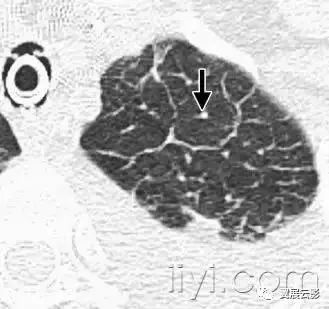

十八、小叶中心性:

解剖:小叶中心性用于描述次级肺小叶的支气管血管束中心区域。病理学上也用这一术语描述终末小支气管远端,位于呼吸性细支气管和肺泡管中心的病变。

CT:正常次级肺小叶中心的点状或者线状的密度增高影,胸膜下25px范围内最明显,代表小叶内的动脉,直径约1mm。

小叶中心性异常包括(1)结节(2)树芽征,提示小气道病变(3)由于临近间质的增厚或者浸润导致小叶中心结果更加清晰(4)小叶中心性肺气肿导致的异常低密度。

附图为小叶中心性肺气肿